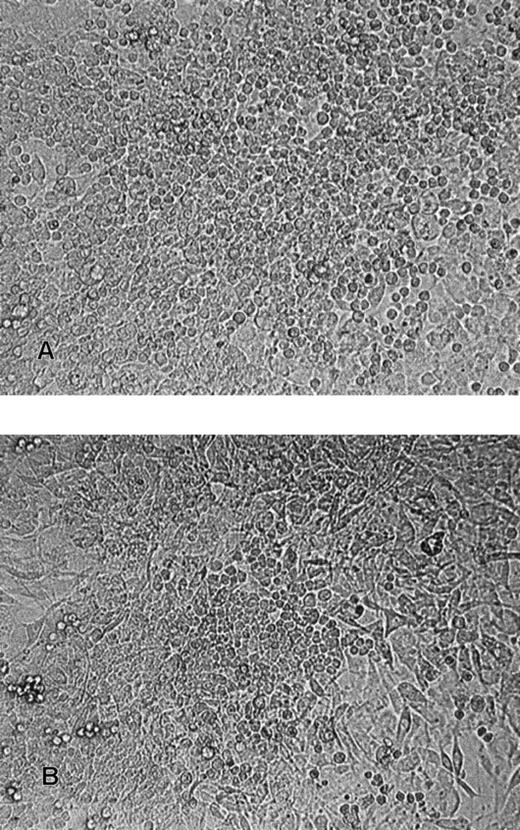

The R366.4 rhesus monkey ES cell line was described previously.12 Cells were maintained in the undifferentiated state by coculture with irradiated murine embryonic feeder cells (Figure 1). ES and feeder cells were cultured in gelatin-coated flasks in Dulbecco modified Eagle medium (Gibco, St Louis, MO) supplemented with 15% fetal-calf serum (FCS; Hyclone, Logan, UT), 1 mM glutamine, 1 × 10−4 M 2-mercaptoethanol, and 2% minimum essential medium amino acids solution (Gibco).

Phase-contrast photomicrograph of an undifferentiated rhesus monkey ES cell colony (magnification, ×100).